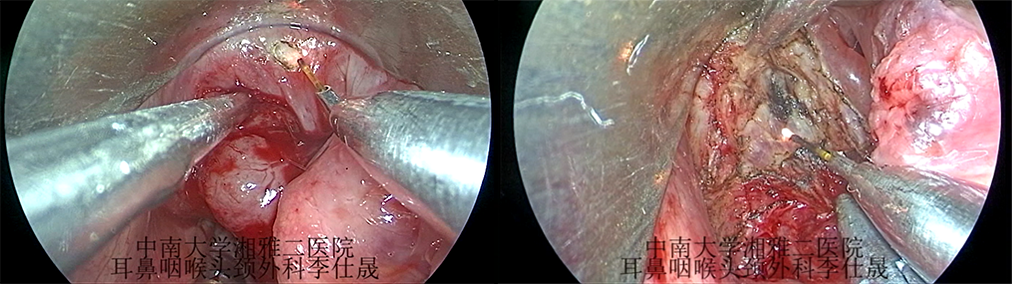

下咽癌传统手术方式主要为开放性手术,必要时需行喉部分切除、全喉切除、全食管切除并一期行组织瓣修复,对患者手术创伤较大,且伴有言语,吞咽功能的损伤。下咽癌的内镜手术可以减少手术创伤、避免气管切开,并最大程度保留患者喉功能及吞咽功能。对于分期较晚的患者术后可以真正快速康复,尽早进行后续的辅助治疗。但下咽癌的内镜手术因为手术术野暴露困难,内镜下解剖不熟悉,常常开展的技术难度较大。湘雅二医院耳鼻咽喉头颈外科李仕晟教授团队探讨了咽喉视频内镜结合光纤激光进行下咽癌治疗。

咽喉视频内镜下光纤激光治疗术

中南大学湘雅二医院耳鼻咽喉头颈外科

李仕晟教授团队

咽喉视频内镜联合光纤激光+颈淋巴结清扫术。

图片